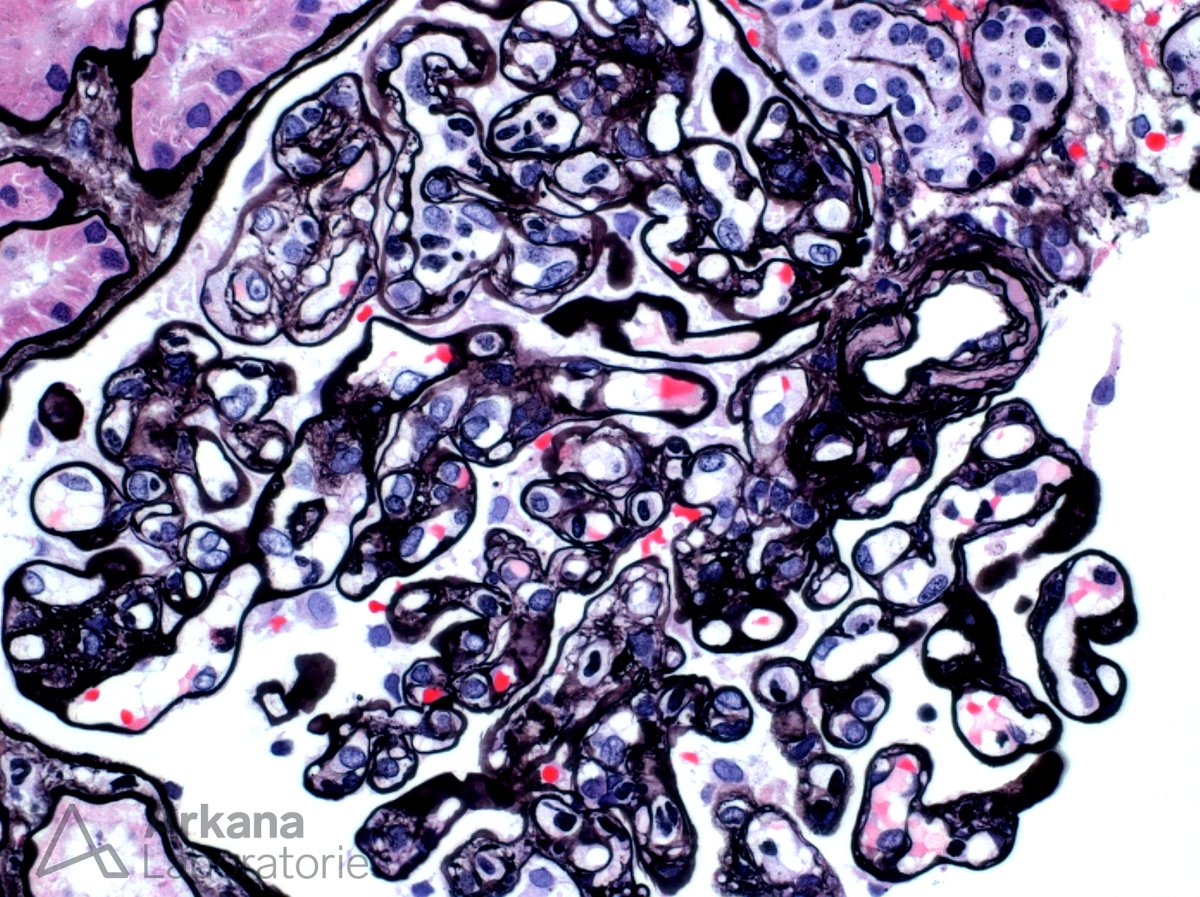

What is your diagnosis based on the EM image provided? #DiagnoseThis #RenalPath #TwitterPath

arkanalabs's tweet image. What is your diagnosis based on the EM image provided? #DiagnoseThis #RenalPath #TwitterPath